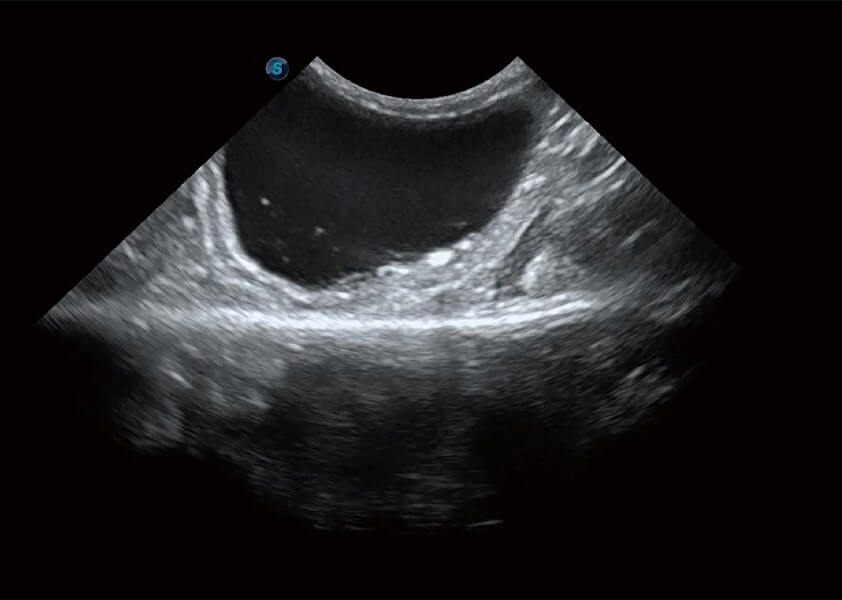

ProPet 60 作为一款高端台式动物超声设备,为动物医生的日常诊断提供了一系列贴合动物临床需求、解决临床实际问题的高级成像功能。凭借全系列高清探头,满足医生对腹部、心脏、生殖、浅表、肌骨等成像的所有需求,切实帮助您提升检查效率,提高诊断信心。

动物是人类最亲密的朋友和最值得信赖的伙伴。db真人体育官网也一直致力于探索动物专用的超声影像解决方案。 全新推出的ProPet系列,是db真人体育官网在动物超声影像智能化、专业化、精准化的一次跨越式革新。动物不能用言语来表述自己的不适,通过超声影像,ProPet系列搭建了动物医生与不同物种沟通的“桥梁”,为动物医生注入了“治愈之力”。